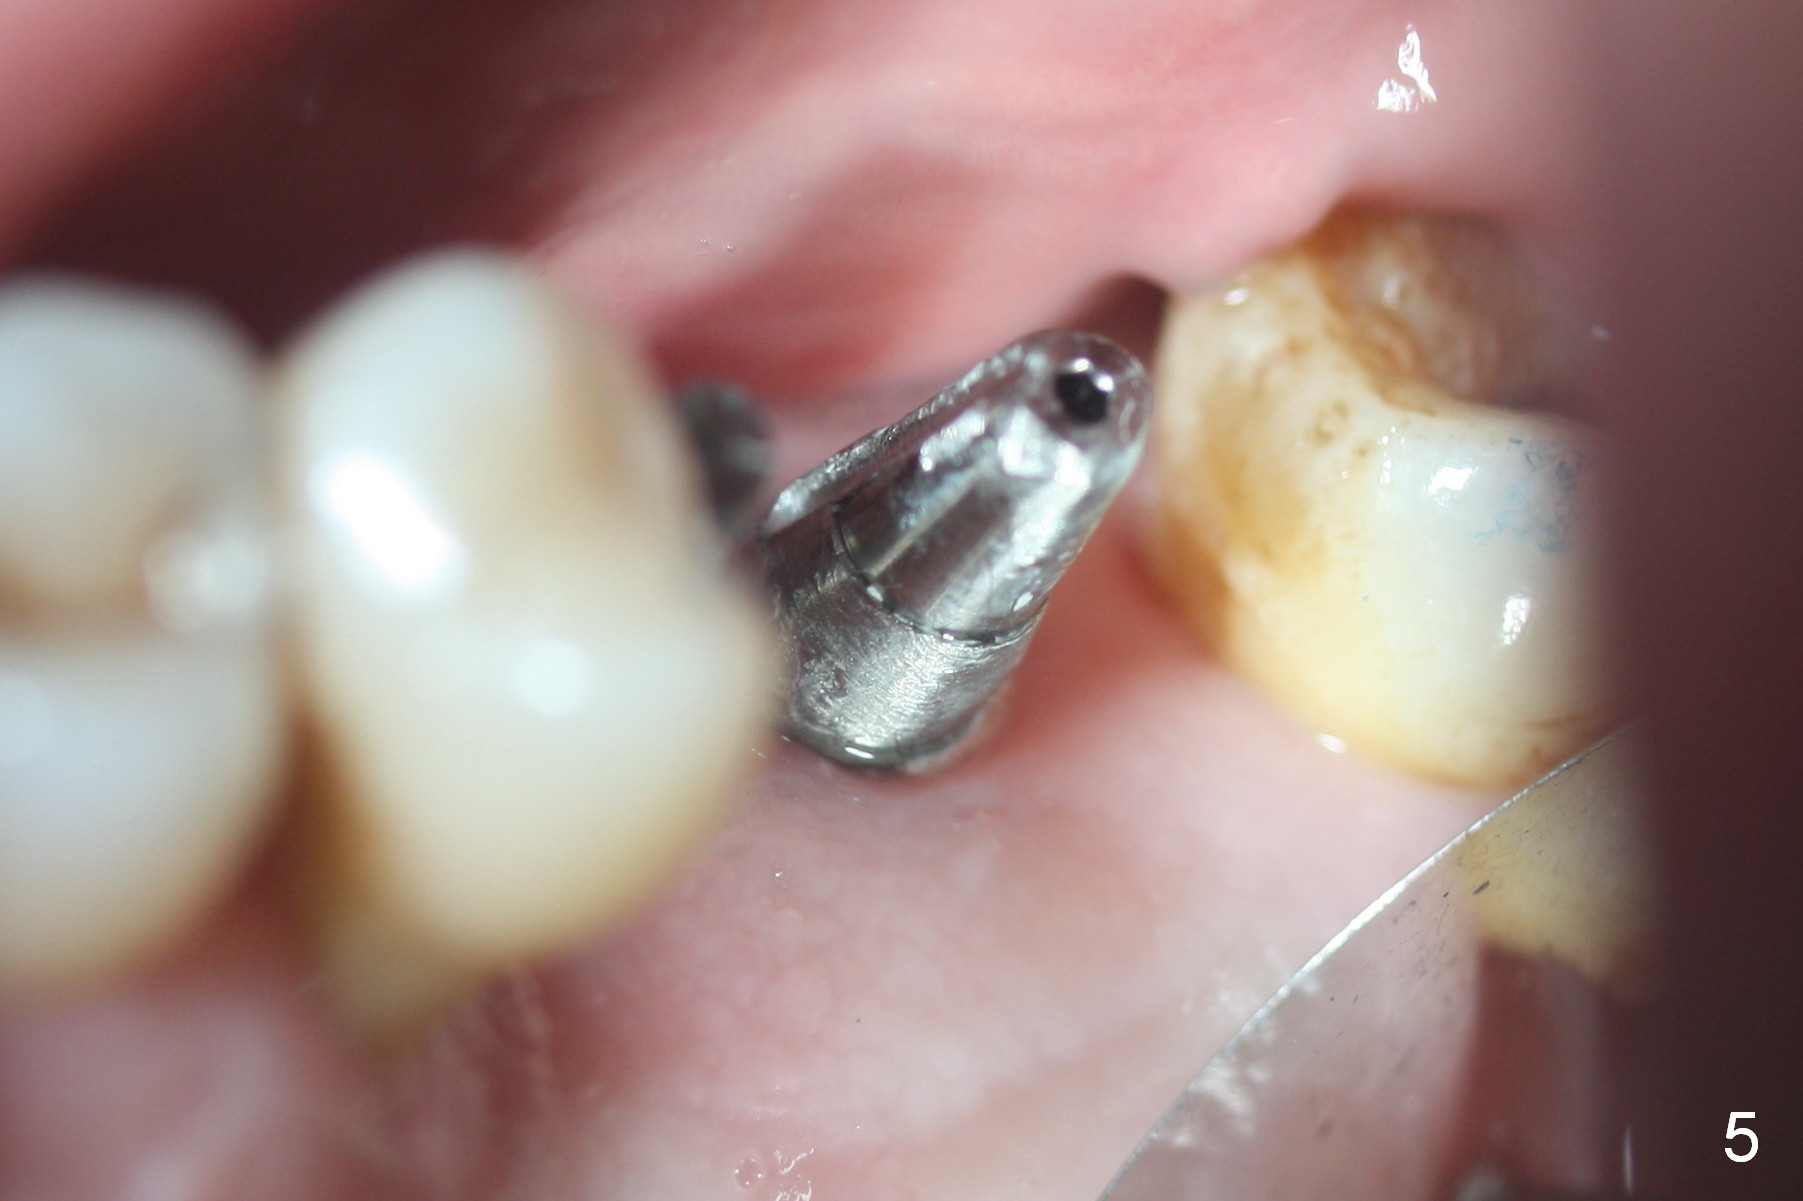

Mild to moderate hemorrhage is encountered as soon as incision is made for the lateral window. It is a concern prior to bone graft and implant placement. Hemorrhage appears to come from the sinus. Bleeding may wash away the graft. Therefore several pieces of Collagen Dressing are inserted into the sinus for hemostasis, followed by placement of Osteogen (Fig.1 *) and implant (5x14 mm, tissue-level). After placement of the 2nd implant, more Osteogen is placed buccal to the implants. Insertion torque is ~ 35 Ncm. Abutments (Fig. 2: 4x5 mm) are placed to hold perio dressing in place (no immediate provisional). In fact, the patient returns within 20 minutes postop because hemorrhage from the incision. Hemostasis is achieved with a few pieces of gauze in the buccal vestibule. Ice pack is recommended. By the evening, the patient reports minimal oozing. When perio dressing is lost 10 days postop, the wound opens (Fig.3). Later the wound heals. It appears that an immediate provisional provides the wound with temporary protection. The abutments without provisional is irritating to the soft tissue (the cheek in this instance). They have to be removed until the implants osteointegrate. PA taken 4 months postop shows the bone in the sinus surrounding the implants (Fig.4 *). The gingiva around the implants looks normal (Fig.5), although there is occasional and mild itching in the skin over the left sinus.